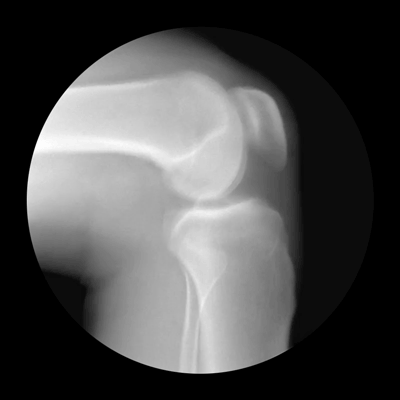

膝关节是人体中大而复杂的关节,它仅仅靠一个狭小的接触面支撑着我们整个身体的重量。

数据显示,我国约有1.2亿人患有骨关节炎,几乎每10人中就有一个。骨关节炎主要分为膝关节炎和髋关节炎,但临床经验表明,膝关节炎占大多数。目前我国50岁以上的人群中,一半人有此困扰,60岁后患病率达60%,到了70岁,几乎每个老年人都会患上此病。

近年来我国骨关节疾病增多,与生活方式密不可分,比如不断增加的体重对膝关节造成巨大负担,不恰当的健身和运动方式加重了创伤性关节炎的发生等。虽然关节疾病并不致命,但患者会因长期疼痛而丧失劳动能力,甚至致残,因此不可忽视。